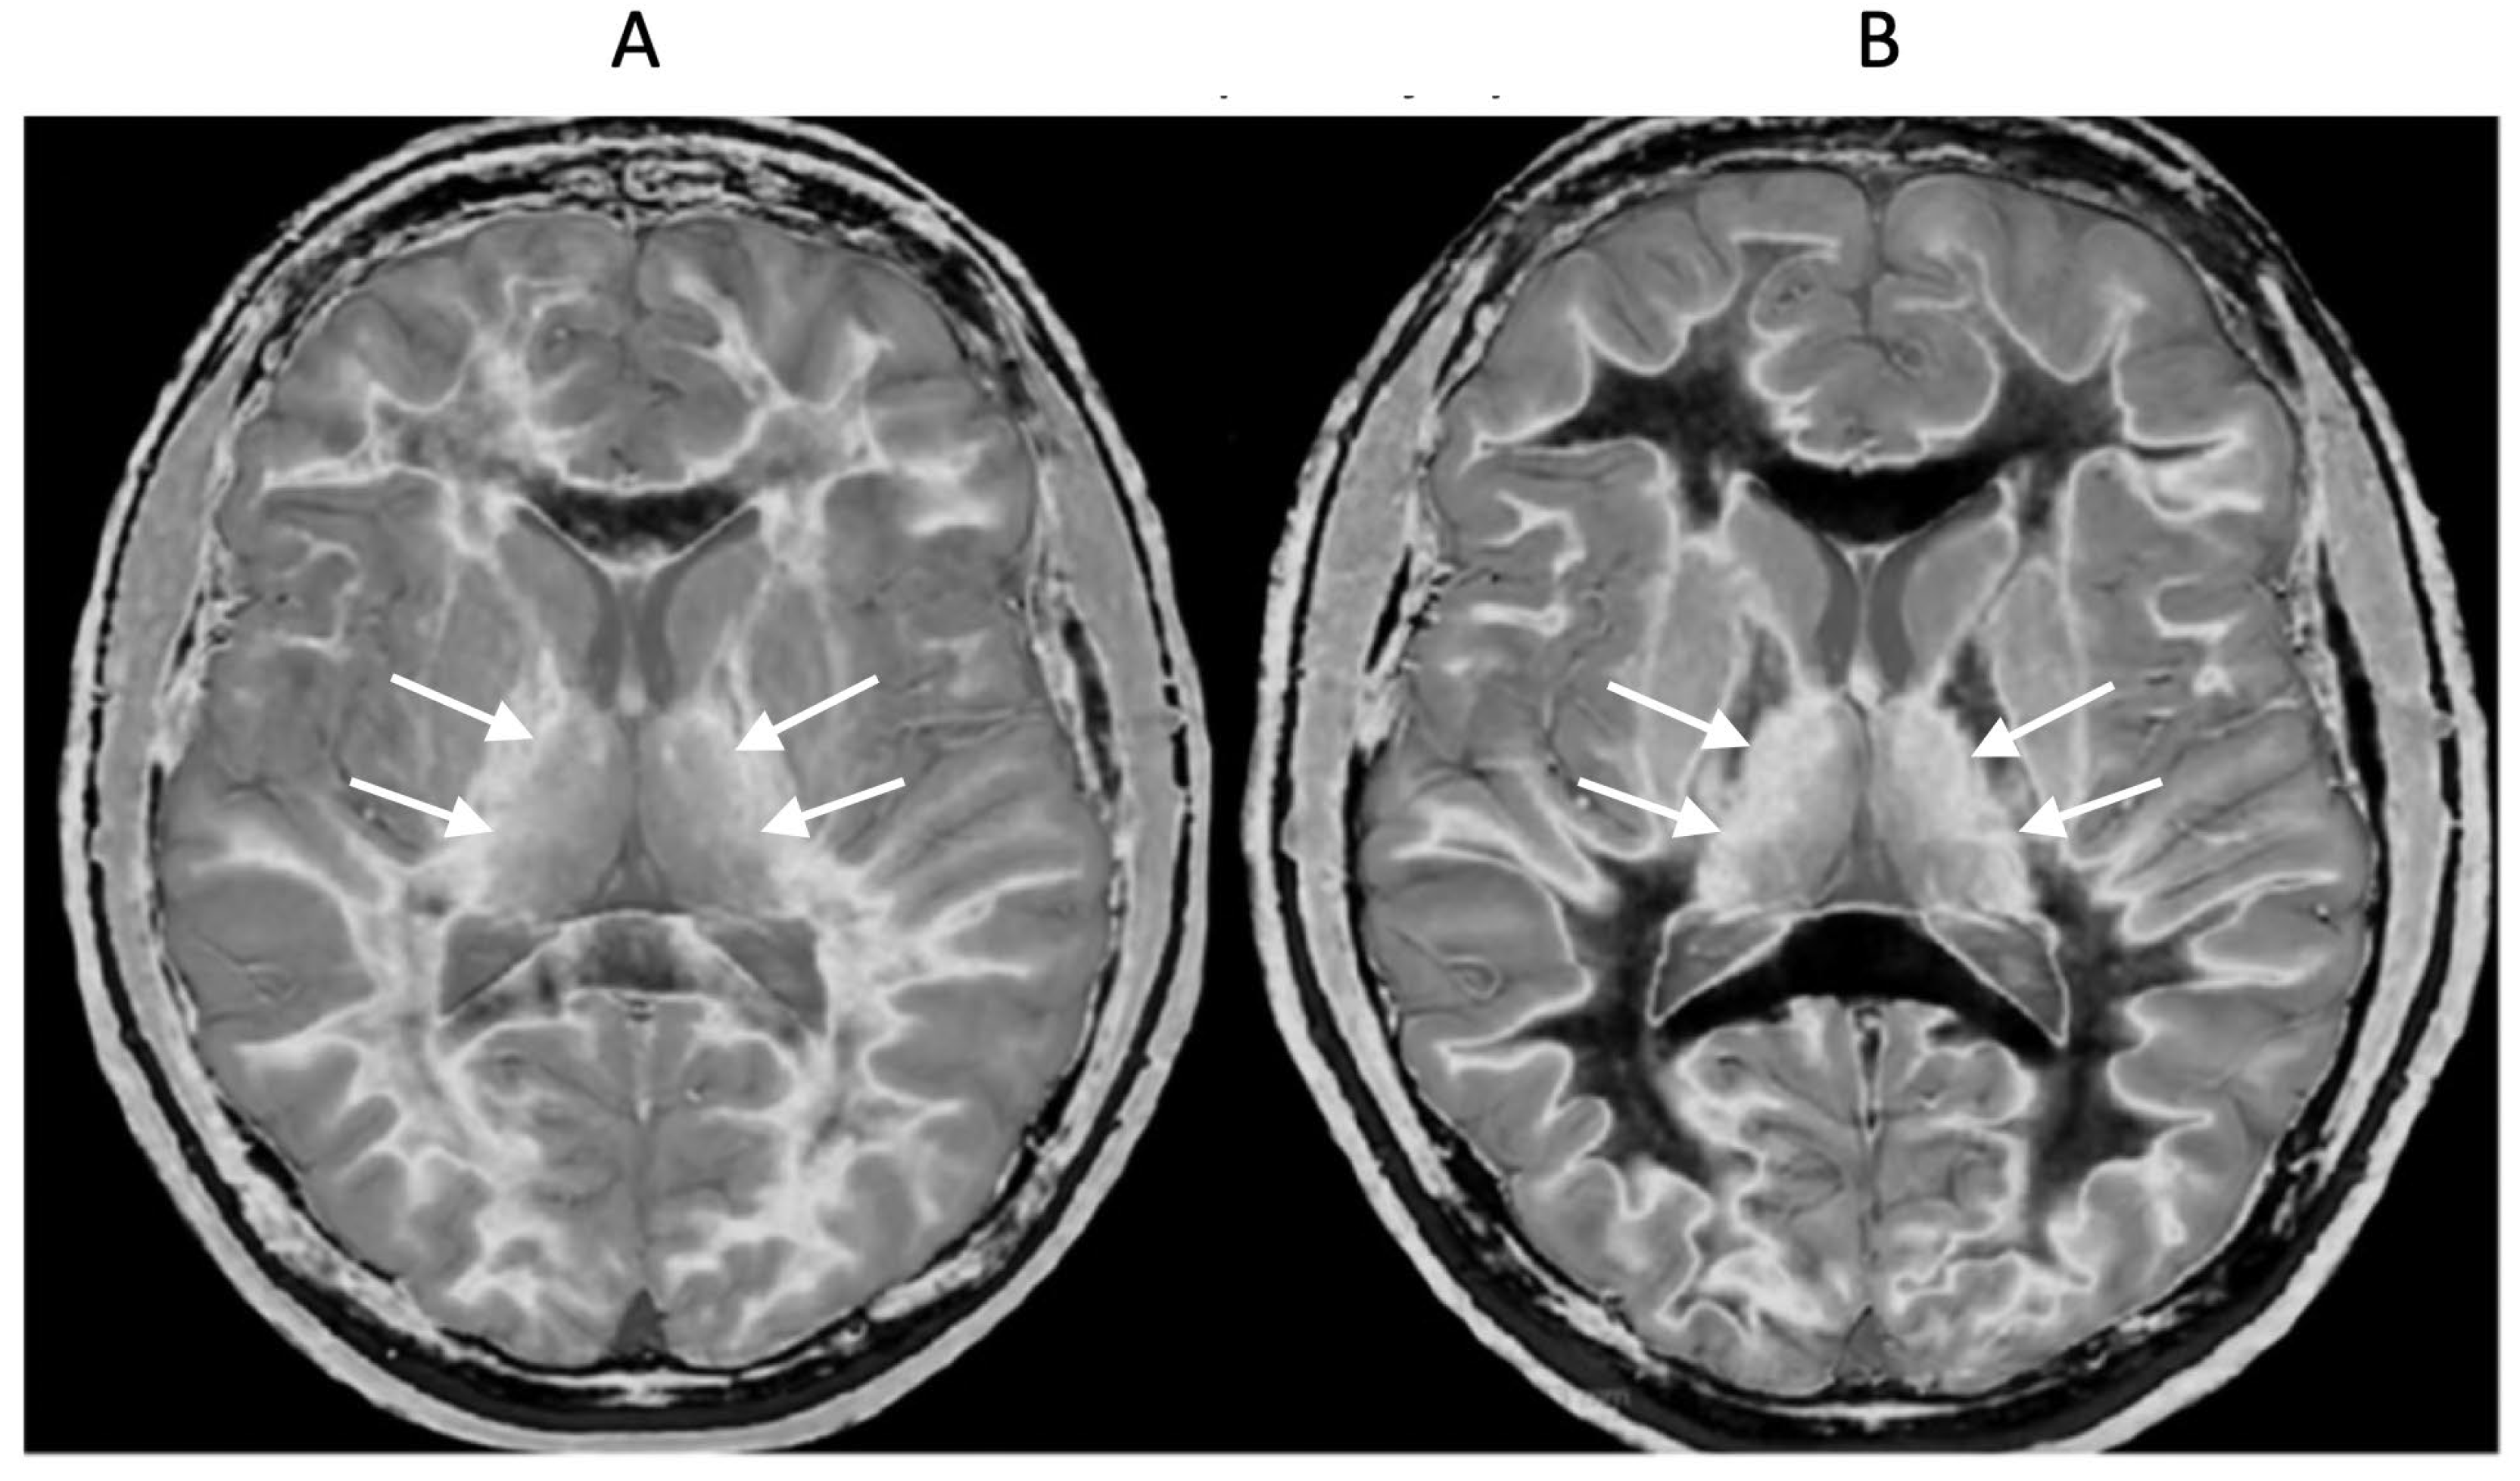

18-year-old patient with mTBI 21h (A) and 64h (B) post injury imaged with the same narrow mD dSIR sequence. In (A) the patient shows a whiteout sign (grade 4 out of 5) with high signal in most of the white matter in the cerebral hemispheres except for the anterior and posterior central corpus callosum. The posterior limb of the internal capsule is high signal. The thalami show low internal contrast from medial to lateral (arrows on lateral margins of the thalami). There is also low external contrast between the lateral margins of the thalami and the adjacent posterior limbs of the internal capsule. On the follow up examination at 64h (B) the whiteout sign has resolved and there is low signal in the white matter including the posterior limbs of the internal capsule (except for the corticospinal tracts). The thalami now show high internal contrast from medial to lateral (arrows on lateral margins of the thalamus) which is the normal appearance at this age. There is now also very high external contrast between the lateral margin of the thalamus and the adjacent posterior limb of the internal capsule. Image (A) shows the grayout sign which is a reduction in the high contrast between the medial and lateral gray matter of the thalamus. The high contrast is restored in (B). No abnormality was seen on the corresponding T2-FLAIR images obtained at both time points.

Figure 12.